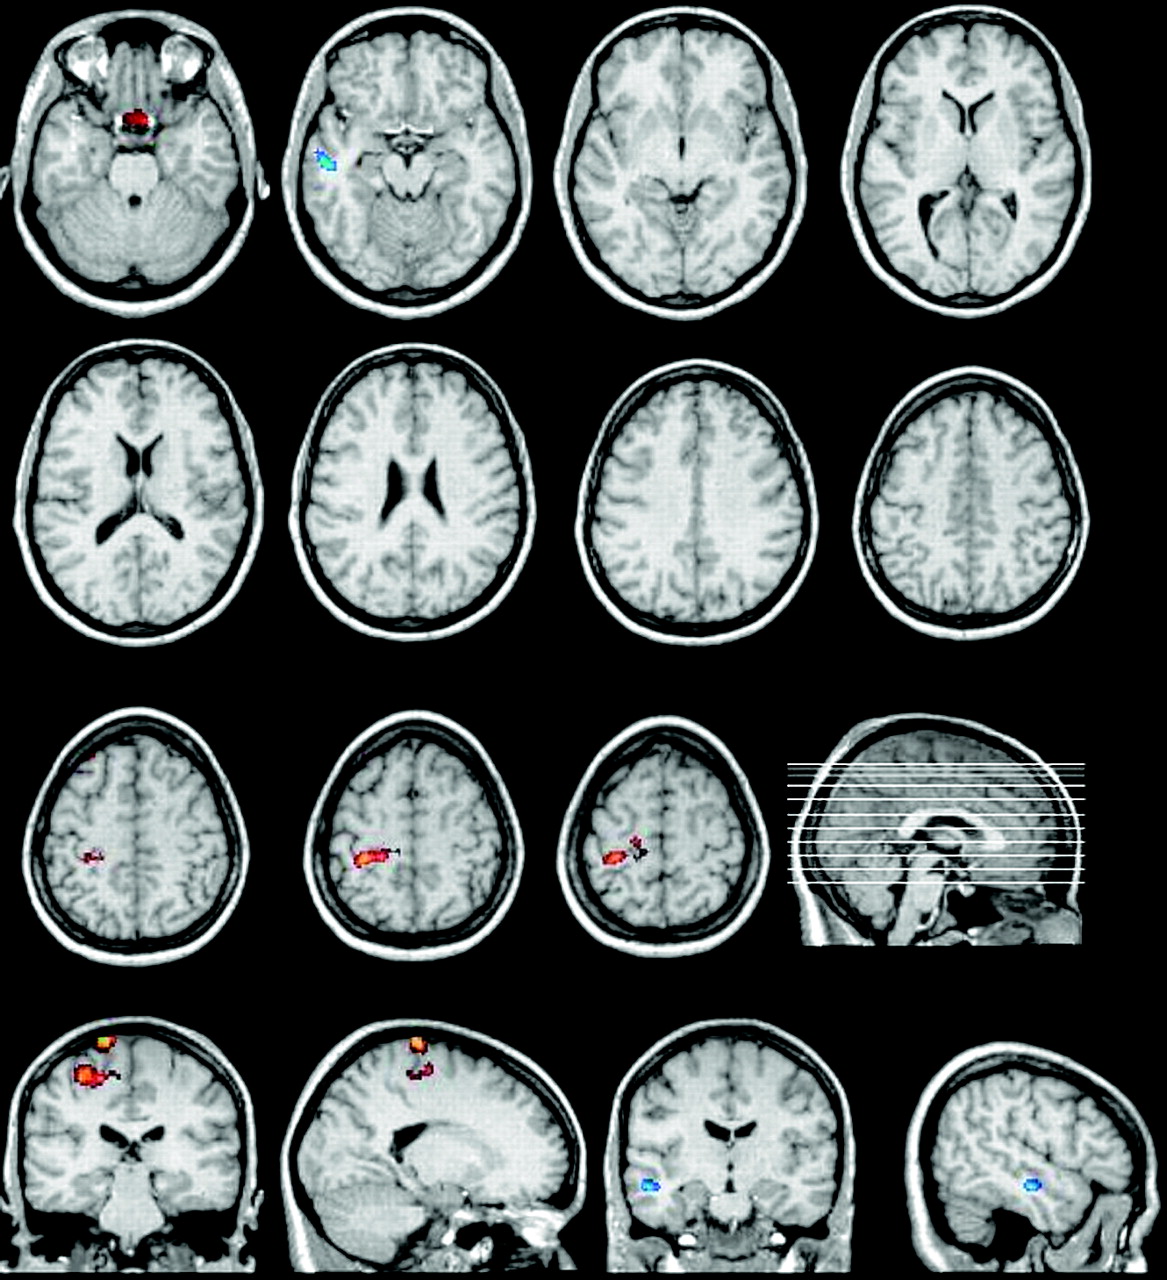

Figures 1 and 2 show all brain regions of increased (orange/red) and decreased (blue) gray matter volume in patients with KS with and without MM, respectively, compared with control subjects.

Regional cortical gray matter volume increase (orange/red) and reduction (blue) in patients with KS and MM relative to control subjects. Significant voxels (height threshold of P < .001, uncorrected for multiple comparisons and an extent threshold of 25 voxels) are superimposed on selected sections of spatially normalized MR images from a control subject. With the hypothesis a priori, areas of increased gray matter are seen around the left central sulcus, in the primary motor cortex, Brodmann area 4 (the cluster with 122 voxels), and the primary somatosensory cortex, area 3 (the cluster with 93 voxels).

Regional cortical gray matter volume increase (orange/red) and reduction (blue) in patients with KS without MM relative to control subjects. Significant voxels (height threshold of P < .001, uncorrected for multiple comparisons and an extent threshold of 25 voxels) are superimposed on selected sections of spatially normalized MR images from a control subject. With the hypothesis a priori, areas of increased gray matter are seen in the left frontal lobe, Brodmann area 6 (the cluster with 304 voxels), and in the right precentral gyrus, contralateral area 4 (the cluster with 27 voxels).